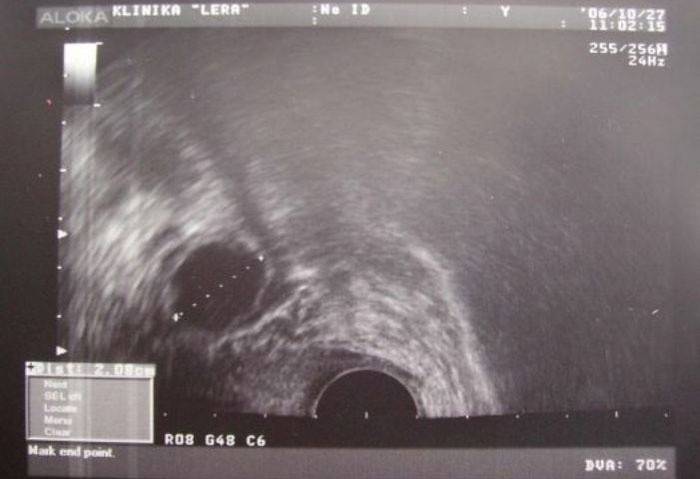

Ultrazvukové vyšetrenie

Metóda ultrazvukovej diagnostiky sa považuje za najpresnejšiu pri určovaní ovulácie. Keď sa žena rozhodla podstúpiť takýto postup, mala by pochopiť, že to nebude obmedzené na jeden deň. Je potrebné vyšetriť sa v strede cyklu niekoľko dní v rade, aby sa zistilo, ako sa dominantný folikul mení a rast. Bezprostredne pred ovuláciou sa na ňom vytvorí malý tuber s vajíčkom. A folikul, ktorý dovtedy dosiahol priemer 2 až 3 cm v priemere, a samotný tubercle je jasne viditeľný na ultrazvukovom prístroji.

Po prasknutí dominantného folikulu opúšťa vajíčko žena brucho a mizne, na tomto mieste vidíme iba luteum corpus a za maternicou sa z neho uvoľní malé množstvo tekutiny. Ak sa ultrazvuková diagnostika vykonáva denne uprostred cyklu, tieto zmeny sa určite zaznamenajú a nebude ťažké vypočítať deň nástupu ovulácie.